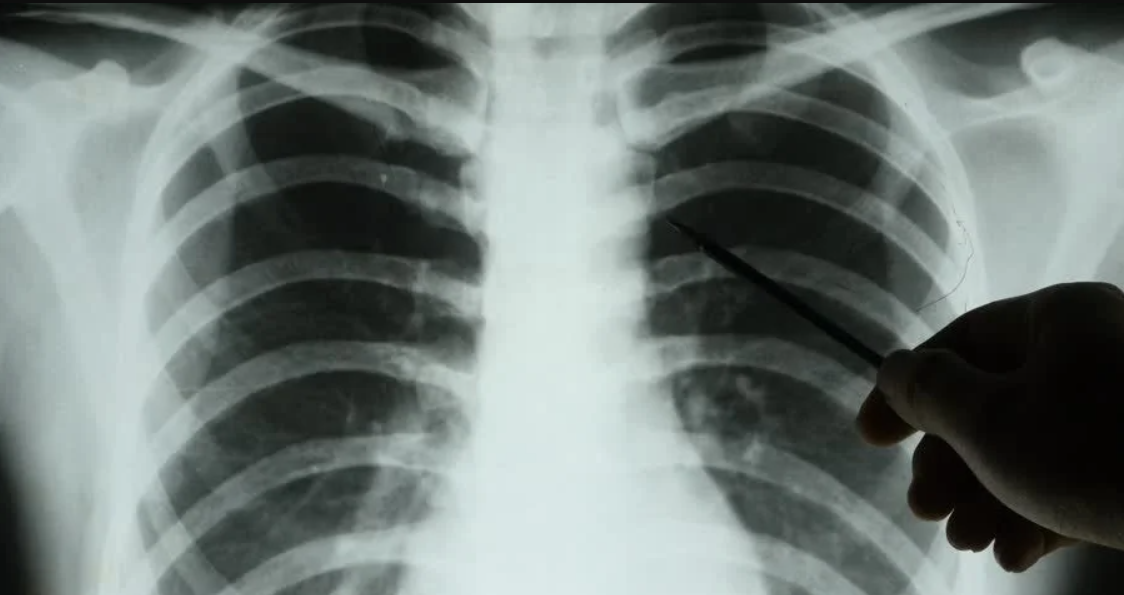

Столичным врачам-рентгенологам теперь доступен сервис на основе технологий искусственного интеллекта (ИИ) для диагностики перелома рёбер, а также для оценки целостности костных структур грудной клетки по данным компьютерной томографии, сообщила пресс-служба мэрии Москвы.

Новое направление в дальнейшем войдет в состав комплексного сервиса ИИ, что позволит определять признаки сразу нескольких патологий в рамках одного исследования. Например, пациенту проводят исследование грудной клетки с подозрением на перелом рёбер, а нейросеть дополнительно проанализирует снимок на возможные патологии лёгких или сердца, сказано в сообщении.